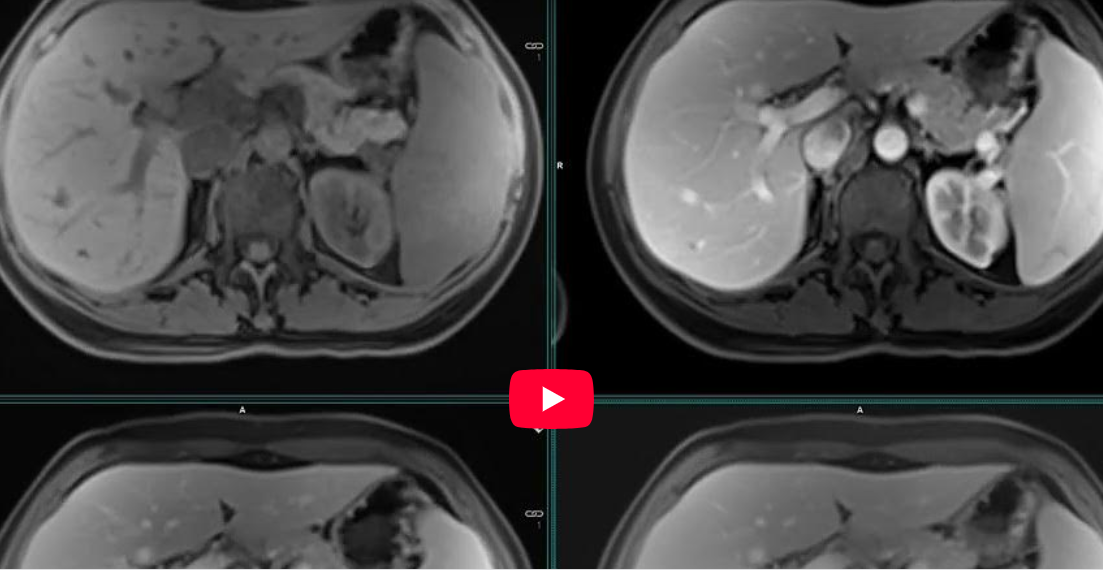

CAZ nr 85: Hiperplazie focală nodulară – investigație cu produs de contrast cu specificitate hepatocitară PRIMOVIST

Video 1: axial T2

Video 2: coronal T2

Video 3: axial in phase / out-of-phase, T2 si T1 vibe precontrast

Video 4: dinamic T1 postcontrast

Video 5: axial T1 postcontrast la 20 de minute

Video 6: coronal T1 postcontrast la 20 de minute

Video 7: axial T1 postcontrast la 30 de minute

Discuţie caz nr 85: Leziunea din segmentul V lob drept are priză precoce de contrast mai intensă comparativ cu parenchimul hepatic de vecinătate apoi devine izointensă. în faza hepatobiliară, la 20 min dupa administrarea agentului de contrast specific hepatocitar, leziunea prezintă captare a agentului de contrast, devenind minim hiperintensă fata de parenchimul hepatic din jur. Deoarece cicatricea centrală nu are hepatocite, nu există captarea agentului de contrast, devenind hipointensă în comparație cu parenchimul hepatic și cu restul leziunii.

IRM este examen de referință, cu indicație de elecție în caracterizarea unui nodul hepatic nou apărut într-un ficat cirotic descoperit printr-o evaluare ecografică de supraveghere. IRM reprezintă cea mai performantă metodă de diagnostic imagistic neinvaziv în caracterizarea nodulilor din ficatul cirotic. Substanță de contrast hepatospecifică permite diagnosticul diferențial al leziunilor hepatice: hemangiom / hiperplazie focală nodulară / adenom / nodul displastic / carcinom și, de asemenea, se eliminină parțial pe cale biliară și astfel se poate aprecia și arborele biliar intra și extrahepatic.